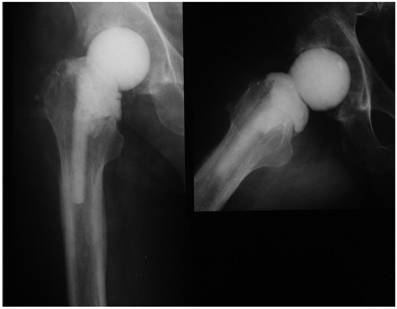

Femoral fractures at the site of hip spacer implantation should be treated when an unstable joint situation results, the outcome of the surgery is endangered or the mobilisation of the patient is hereby limited. Generally, the surgical treatment of these fractures should be planned taking into consideration any further surgical revisions or the later prosthesis reimplantation. If possible, the insertion of any metallic implants should be avoided if the infection is not completely eradicated for avoidance of an infection persistence or reinfection. In difficult cases with a nonsupportive proximal femur part, the treatment's choice should be made under consideration of both infection sanitation and fracture management. In cases, where the spacer stem does not exceed 10 cm (in the majority of the cases), alternative reconstructive methods should be performed. In our experience, the use of modular prosthesis systems or long nails with an antibiotic-loaded cement mantle and a spacer head is an elegant method that treats both the fracture and the infection (Figure 8). At the time of prosthesis reimplantation, the spacer head can be easily removed and the modular prosthesis parts (neck and head) placed. This procedure offers a stable fracture treatment and facilitates the prosthesis reimplantation regarding shorter surgery time, less blood loss and no need for femoral exposure. Furthermore, this technique can be also applied in cases with large and extensive osseous defects of the proximal femur due to the prosthesis loosening where a stable fixation of the spacer to the proximal femur according to the usual fixation techniques is not possible (Figure 9). Although some hip spacers have the advantage of a long stem (e.g. PROSTALAC) [8] and can be treated to a similar manner as shown in Figure 8, not every clinic has these spacers in hold; the above mentioned technique is a noble alternative to these constructs.

Figure 8

Left: Femoral fracture at the site of hip spacer implantation. Right: Treatment consisted of spacer removal, and insertion of a cement-coated modular prosthesis with a spacer head. The cement mantle of the prosthesis is also antibiotic-loaded according to the sensitivity profile of the causative organism. After infection eradication, the spacer head has been removed and a metallic head with an acetabular cup implanted. This procedure offers a stable fracture treatment and facilitates the prosthesis reimplantation regarding shorter surgery time, less blood loss and no need for femoral exposure. The remaining intrapelvic cement has no disadvantage regarding the infection eradication and might be associated with severe intraoperative complications in case of a removal trial.

Figure 9

Large osseous defect of the proximal femur following extensive prosthesis loosening. Treatment consisted of prosthesis removal, debridement, pulsatile lavage, and insertion of a long femoral nail with an antibiotic-loaded cement mantle and a spacer on top.